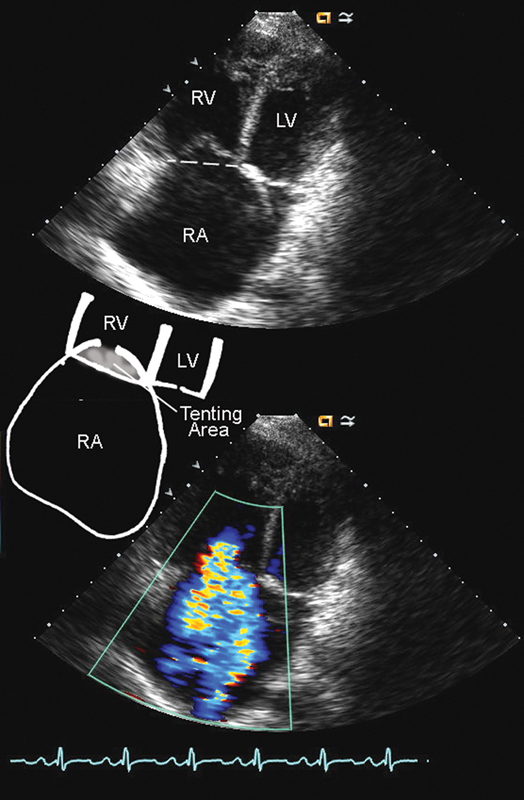

فحوصات تشخيصية لبعض امراض القلب والشرايين التاجية